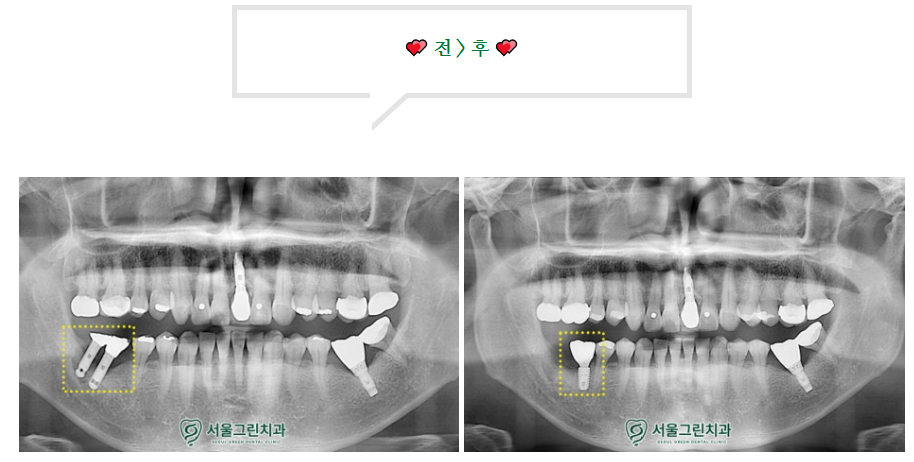

엑스레이를 촬영해 체크해보니

임플란트 주변으로

염증이 퍼져 있는걸 확인할 수 있습니다.

전형적인 임플란트 주위염인 상태로

치료가 불가능한 상태여서

결국 제거를 해야 하는 상황이었는데요..!

발거 후 주위 염증이 사라지고

건강한 잇몸으로 돌아온다면

좀더 관리가 잘될 수 있는

최적의 위치에 임플란트를 심고

주변에 뼈가 부족하다면

치조골 이식도 같이 진행하게 된답니다.